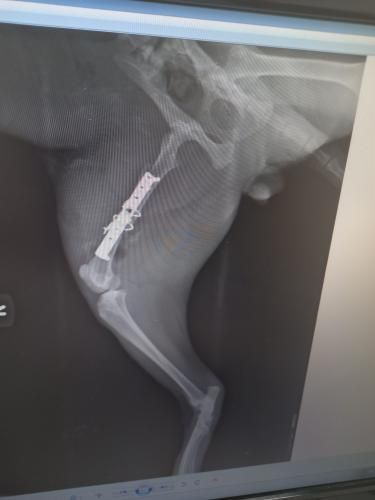

Ahojte...chilli nafotím v priebehu vykendu,celkom sa to pohlo...inak dnes operovali nášho najmladšieho pomocníka...trieštivá zlomenina stehennej kosti.nejaky dobrý človek ho strelil vzduchovkou...

A prestrelil mu kosť

Ten biely fľak pri zlomenine je brok...

Takže o zábavu postarané tak na mesiac a uvidí sa ako sa to zhojí no...